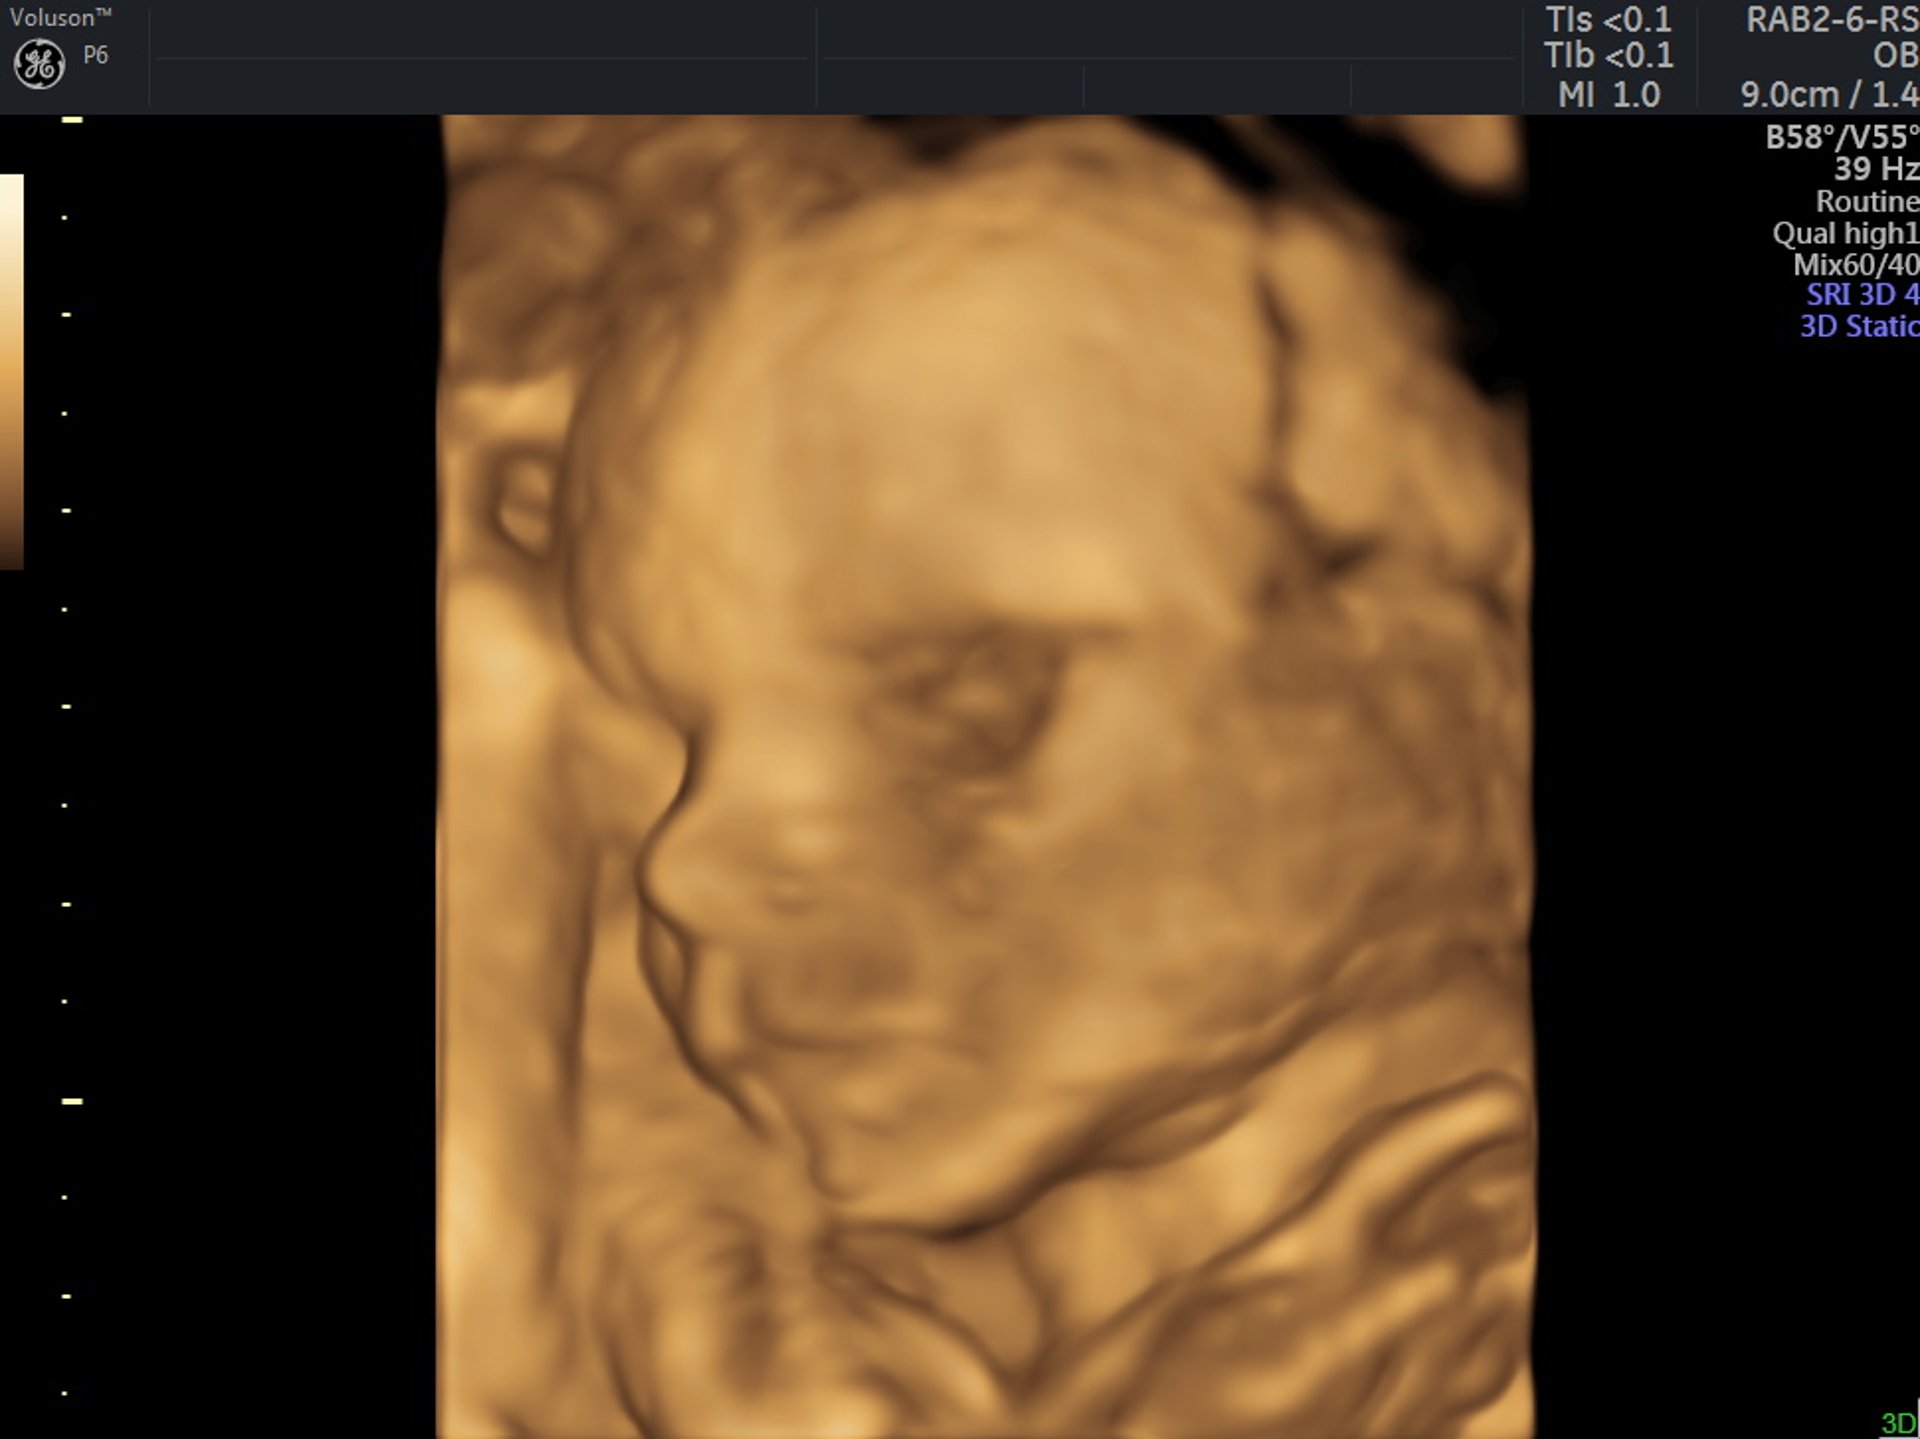

Genetikai szűrővizsgálatok

I., II. és III. trimeszterben